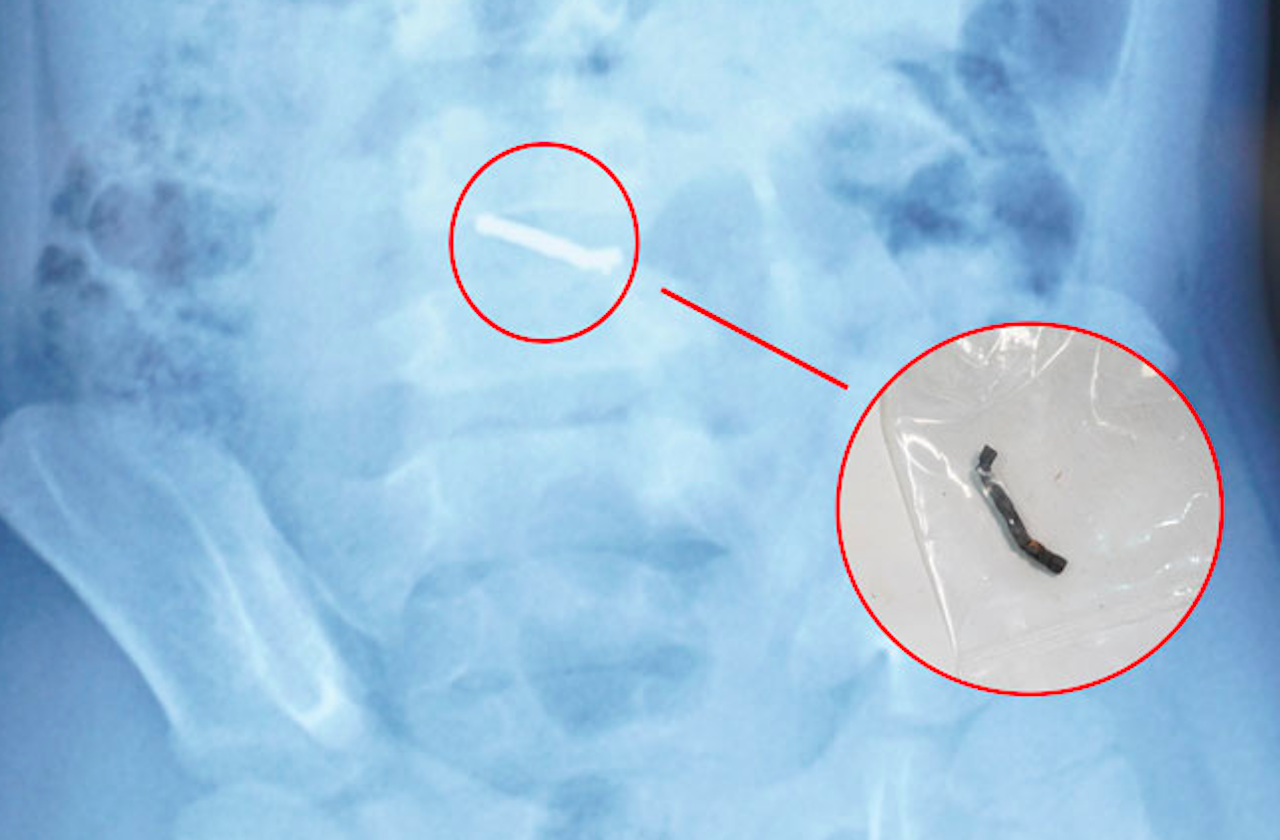

Trong thời gian dùng thuốc tại nhà, các triệu chứng không cải thiện, trẻ được tái khám và chụp x-quang thì phát hiện dị vật trong ổ bụng. Sau đó, trẻ được chuyển đến Bệnh viện Nhi Trung ương để tiếp tục theo dõi và điều trị.

Tại Bệnh viện Nhi Trung ương, sau khi thực hiện các xét nghiệm và chẩn đoán hình ảnh cận lâm sàng và theo dõi diễn biến, các bác sĩ nhận thấy dị vật trong đường tiêu hóa không di chuyển theo thời gian. Thông thường, dị vật trong đường tiêu hóa sẽ được nhu động ruột đẩy dần ra ngoài. Tuy nhiên, trong trường hợp này, dị vật không di chuyển.

Từ thông tin gia đình cung cấp về loại đồ chơi có các viên nam châm nhỏ có thể hút vào nhau, các bác sĩ chẩn đoán trẻ đã nuốt phải nhiều viên nam châm trong nhiều thời điểm. Sau khi xác định dị vật có từ tính và không thể tự đào thải ra ngoài, các bác sĩ đã tiến hành phẫu thuật cho trẻ.

Trong quá trình phẫu thuật, các bác sĩ phát hiện nhiều viên nam châm nhỏ dính vào nhau thành một chuỗi, gây thủng ruột. Các bác sĩ phẫu thuật đã tiến hành lấy dị vật, khâu lỗ thủng và đặt dẫn lưu. Sau 4 ngày, bệnh nhi đã sinh hoạt bình thường, bắt đầu được tập ăn trở lại và dự kiến sẽ được ra viện trong một vài ngày tới.